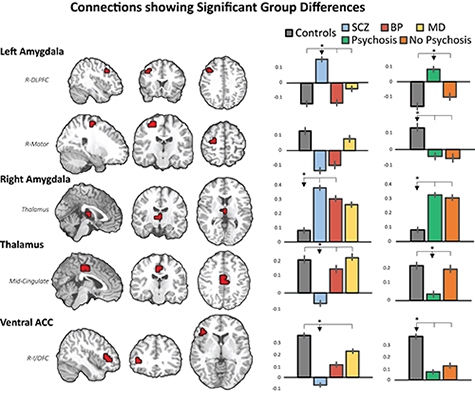

Specifically, we have studied offspring of mothers diagnosed with psychiatric disorders such as schizophrenia, bipolar disorder, and so on (representing genetic risks) and mothers using recreational drugs such as cocaine and marijuana during pregnancy (representing environmental risks). By imaging their offspring at the neonatal stage, our design minimizes other postnatal environmental confounds (caregiving quality, socioeconomic status, etc.) commonly associated with maternal psychiatric disorders and/or substance abuse, thus enabling us to delineate the more-direct brain mechanisms associated with genetic or environmental risks. Our results consistently demonstrate that critical functional circuits already show risk-related abnormalities in neonates. More importantly, these functional circuit deficits significantly predict later behavior outcomes.Based on the Gao Lab's extensive experience in studying normal brain functional development during infancy, we have recently begun to look into abnormal development due to genetic and/or environmental risks.

These studies demonstrate that the footprint of genetic and environmental risks on the brain's functional organization can be detected as early as in neonates. Such early detection is critical for the development of potential biomarkers for early identification of risks and for guiding intervention.

| Functional connectivity changes in neonates whose mothers were diagnosed with schizophrenia (SCZ), bipolar disorder (BP), and mood-disorder not-otherwise-specified (MD), compared with normal controls (Controls). |